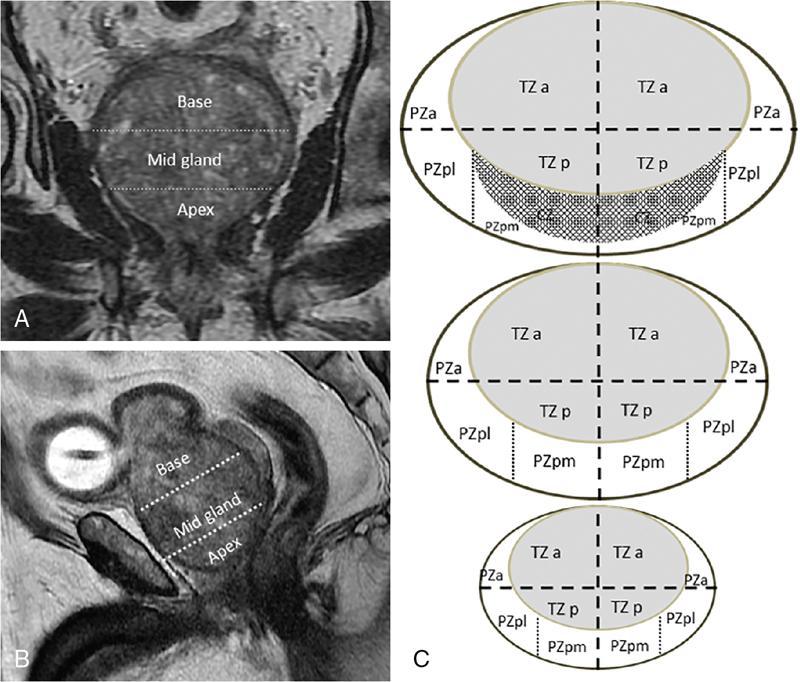

MULTIPARAMETRIC MRI OF THE PROSTRATE Dayala Sundaram Worldwide prostate cancer is the most common solid organ malignancy and the second most common cancer in men. The incidence of prostate cancer in India is 3.9 per 100,000 men and contributes 9% of all cancer-related mortality. Traditionally, serum prostate specific antigen (PSA) and digital rectal examination (DRE) are used as screening tools, and systematic transrectal ultrasound (TRUS)-guided biopsy is considered as the gold standard for confirmation for the detection of cancer prostate. Nevertheless, this combined approach has led to the risk of overdiagnosis and overtreatment of clinically insignificant low volume and indolent tumours. On the other hand, tumour in the anterior aspect of the gland tends to be missed by TRUS-guided biopsy until they grow to a substantial size and reach within 15–20 mm from the posterior margin, leading to delayed diagnosis. Moreover, systematic TRUS biopsy has also proven to underestimate the final Gleason score of the tumour following radical prostatectomy, leading to inaccurate triaging and selection of therapeutic options. Multiparametric magnetic resonance imaging (mpMRI) changed the paradigms on prostate cancer detection. It struck a balance between underdiagnosis and overdiagnosis with a clinical priority not to miss any clinically significant cancer (Gleason score ≥4 + 3, and/or volume ≥0.5 cc, and/or extraprostatic extension). Initially, MRI was not used for the primary detection of the tumour, but it was mainly used for locoregional staging in biopsy-proven patients since it provided only morphologic information with T1-weighted imaging (TIW) and T2-weighted imaging (T2WI). Ever since the introduction of mpMRI, which combines the morphological assessment of T2WI and molecular and physiologic assessment by diffusion-weighted imaging (DWI) and dynamic contrast-enhanced (DCE) imaging, it has been used in primary tumour detection as well as staging. Over the period, mpMRI has been proven to have high sensitivity and negative predictive value (NPV) in diagnosing clinically significant prostate cancer, however, with more variable specificity. A positive association has also been established between abnormal mpMRI and increased tumour volume and high grade. Overall, the introduction of mpMRI has changed the traditional diagnostic pathway in the management of prostate cancer (Fig. 11.24.1.1). Efforts were taken to improve the global standardization in image acquisition, interpretation and reporting of mpMRI of prostate and prostate imaging reporting and data system (PI-RADS) was introduced in 2012. T1WI, T2WI, DWI, DCE and spectroscopy were identified as the key sequences. In 2015, PI-RADS version 2 (v2) was released with the inclusion of key advancements in image acquisition and incorporation of a five-point final assessment scoring system for peripheral zone (PZ) and transition zone (TZ). Spectroscopy was excluded in PI-RADS v2. The recent update, PI-RADS version 2.1 (v2.1), proposed in 2019, endorses small adjustments to obviate ambiguities in the scoring system and reduces inter-reader variability. PI-RADS is intended for detection, localization and risk stratification in patients with suspected cancer in the prostate gland and staging the confirmed cases. However, detection of recurrence, progression during active surveillance and evaluation of other parts of the body (e.g. skeletal system) are not included in PI-RADS. In mpMRI following recent TRUS-guided biopsy, the postbiopsy haemorrhage in the prostate gland and seminal vesicles may confound assessment. Since the postbiopsy changes may persist for many months, and it may not always be feasible or necessary to postpone the MRI examination. Moreover, if mpMRI is performed following a negative TRUS biopsy, the possibility for clinically significant prostate cancer (csPCa) at the site of postbiopsy haemorrhage is less likely without corresponding suspicious finding on MRI. If postbiopsy haemorrhage or inflammation adversely affects the interpretation of a study, then at least 6 weeks or longer should be considered for follow-up. MR spectroscopy was recommended in PI-RADS v1. However, no incremental value was acclaimed by MR spectroscopy in routine clinical use despite prolonging the duration of the study and requirement of dedicated software. Hence, MR spectroscopy was not included in PI-RADS v2. High-resolution T2WI is the fundamental sequence in mpMRI useful to identify the zonal anatomy, assess abnormality within the gland, seminal vesicle invasion, extraprostatic extension and nodal metastasis. Due to high glandular content, the normal PZ appears as homogeneously hyperintense. Whereas, due to high cellularity and less water content, the clinically significant cancer in the PZ usually appears as a hypointense focus. Moreover, the decrease in intensity on T2WI is proven to be positively associated with the aggressiveness of the tumour. Due to the high cellularity, the normal TZ also appears heterogeneously hypointense, which makes the detection of cancer difficult in the TZ. Caveats: Benign conditions like prostatitis, haemorrhage, glandular hypertrophy, postbiopsy scar and post-therapy changes may show similar hypointensity. Benign stromal elements may appear hypointense in the TZ. Scoring: PI-RADS v2.1 recommends separate five-point scoring system for lesions in PZ and TZ based on T2WI. However, T2WI scoring is used only in overall risk assessment of TZ lesions and caries no significance in PZ lesions (Table 11.24.1.1). DWI quantifies the degree of the random movement of water molecules within the prostate. Due to high cellularity, the motion of the water molecules is inhibited within the tumour, which is seen as a high signal on DWI and low signal intensity on apparent diffusion coefficient (ADC) maps. It is recommended to obtain one low b-value image set at 50–100 s/mm2 and one intermediate b-value image set at 800–1000 s/mm2. b50 is used instead of b0 to prevent shine through of vessels. A high b-value image set with ≥1400 s/mm2 is also mandatory, which preferably should be acquired separately or calculated from low and intermediate b-value images. According to PI-RADS v2.1, high b-value image (≥1400 s/mm2) must be used for interpretation. In the high b-value image (≥1,400 s/mm2), background signal from the nonmalignant tissue is suppressed; hence, the sensitivity and accuracy are increased (Fig. 11.24.1.2). Moreover, the degree of signal reduction on ADC map has been proven to be positively associated with increasing Gleason score. However, at high b-value, the SNR decreases, to compensate for the signal loss, it is essential to increase the number of excitations (NEX) with increasing b-value. Caveats: Some benign hyperplastic (BPH) nodules in the TZ may show restricted diffusion. Susceptibility artefacts may be encountered in DWI by air in the rectum or metal hip prosthesis, which can be minimized by using short TE. Scoring: Each suspicious lesion in the PZ and TZ are scored based on five-point scoring system (Table 11.24.1.2). DCE involves the rapid acquisition of T1WI after the administration of intravenous Ga-based contrast agent. Due to tumour angiogenesis prostate cancers often demonstrate early enhancement compared to normal tissue. Some of the tumour shows early washout, while others may retain contrast for a longer duration. DCE, in combination of T2WI and DWI, further increases the sensitivity for detection of csPCa, particularly in men with lower PSA levels (<10 ng/mL) and for less experienced readers. DCE also plays an essential role in the assessment of local recurrence following prior radical treatment or focal therapy. Caveats: Presence of early enhancement alone not definitive for cancer and the absence of early enhancement does not exclude the possibility completely. Diffuse enhancement may be noted in prostatitis. DCE has a limited role in assessing lesions in the TZ. Scoring: Lesions in the PZ are assessed with positive or negative scoring. A negative score on DCE not only indicates the absence of early enhancement but also includes diffuse or multifocal enhancement in the gland (Table 11.24.1.3). Useful to detect biopsy-related haemorrhage within the gland or seminal vesicles and to detect nodal and skeletal metastasis. Tumour focus will not show any significant changes on T1WI. With a broad range of MRI scanners with different static field strength, receiving coil technologies and software platforms, it is difficult to achieve a bespoke mpMRI prostate imaging guidance for every MR system. Hence, individual parameters like repetition time (TR)/echo time (TE) acquisition matrices should be tailored for every system to obtain high-resolution images. The number of slices can depend on the size of the prostate gland. In benign prostatic hyperplasia (BPH), the central zone (CZ) is compressed and displaced by the enlarged TZ. The prostatic pseudocapsule or surgical capsule is a thin hypointense rim at the interface of TZ and PZ. Seminal vesicles appear hyperintense on T2WI. Neurovascular bundles are noted in the posterolateral aspect at 5-o’clock and 7-o’clock positions (Fig. 11.24.1.3). PI-RADS v2.1 segmentation model has 41 sectors: 38 for the prostate, 2 for the seminal vesicles and 1 for the external urethral sphincter. Prostate is divided into right/left by a vertical line through the centre and from superior to inferior, divided into three regional parts: the base, the mid gland and the apex. PZ on both sides at each level subdivided into three sections: anterior (a), medial posterior (mp) and lateral posterior (lp). Similarly, the TZ on both sides at each level subdivided into two sections: anterior (a) and posterior (p) (Fig. 11.24.1.4). Sector map may help the radiologists, urologists and pathologists to precisely localize findings described in mpMRI reports and provide a roadmap for MRI targeted biopsy/therapy and for surgical dissection. It can be used as a visual aid for discussions with patients regarding biopsy and therapeutic options. Each suspicious lesion is scored individually based upon the zonal location of the lesion. The PZ lesions are scored with DWI and ADC, and the TZ lesions are scored with T2WI and DWI. The individual scores are used to get a combined overall risk assessment category score from 1 to 5. Percentage of malignancy for each category is given in Table 11.24.1.5. The dominant sequence in the PZ is DWI, and the lesions in the PZ are scored from 1 to 5 based on ADC map and corresponding DWI. DCE plays a secondary role only in assessing the equivocal cases (PI-RADS 3) in the PZ. A lesion with PI-RADS score 3 based on ADC map and DWI can be upgraded to overall assessment PI-RADS category 4 if it shows early enhancement on DCE (Fig. 11.24.1.5). Scoring criteria should be firmly adhered to avoid the potential scoring of inflammation (score 2) as score 3, which in turn can be upgraded to overall PI-RADS category 4 if showing early enhancement on DCE. Marked hyperintensity on DWI is defined as more pronounced signal change than any other focus in the same zone. Lesions in the TZ are assessed with T2WI and DWI (Fig. 11.24.1.6). No significant role for DCE in TZ lesions. Since T2W is the primary determining sequence if the lesion has a T2W score of 4 and DWI score of 2, the final assessment category should be 4. Shape and margin of the lesion are the critical features for evaluation. Focal lesions, nodules or regions that differ from the imaging characteristics of the background should be scored. If multiple nodules with similar degrees of restricted diffusion scattered throughout the TZ, they should not be scored since they make restricted diffusion as a feature of background. The classic-appearing encapsulated BPH nodules are considered as a normal variant and assigned PI-RADS score 1. BPH nodules with high cellularity may have marked restricted diffusion, still can be categorized as score 1 with the help of T2WI. The atypical nodules, which are not fully encapsulated, and hypointense areas between the nodules are classified under score 2. If they have a marked restricted diffusion (DWI score of ≥4), they can be upgraded to PI-RADS 3 overall assessment category. Lesions in category 3 can be upgraded to category 4 if they demonstrate a DWI score of 5 (i.e. size >15 mm or invasive behaviour) (Fig. 11.24.1.7).

Sector map